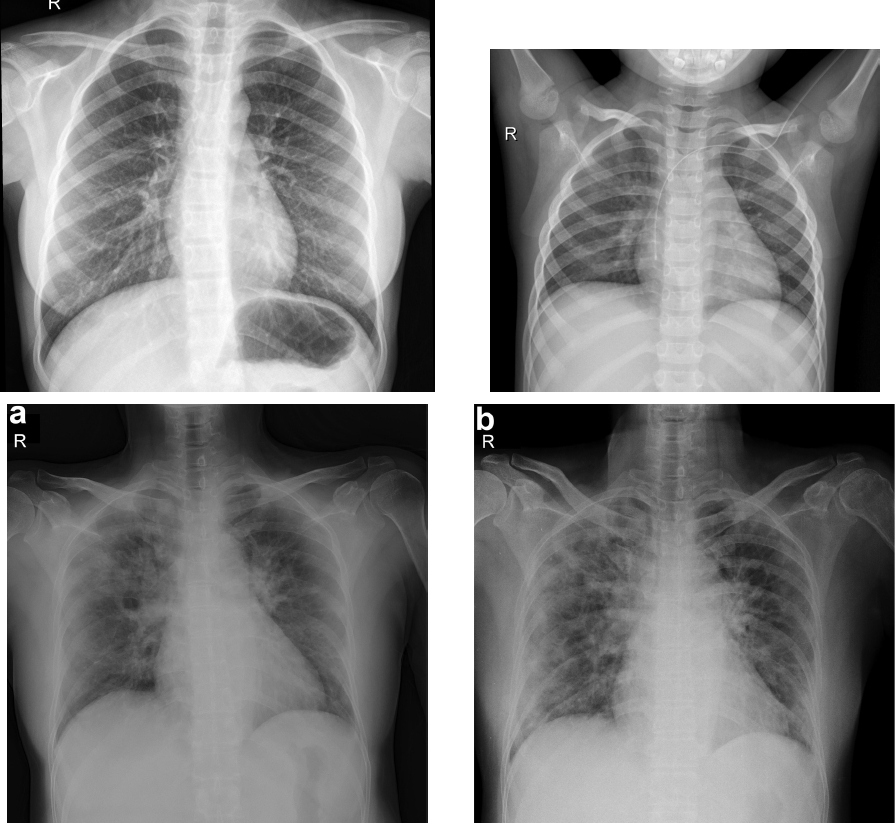

The images dataset used in this work is obtained by Adrian Rosebrock and available in (PyImageSearch.com). This dataset is composed of 50 X-ray images divided into two categories: 25 images represents normal chest and the remaining 25 are classed as COVID 19. The images have different size. Figure 1 illustrated some chest X-ray images.